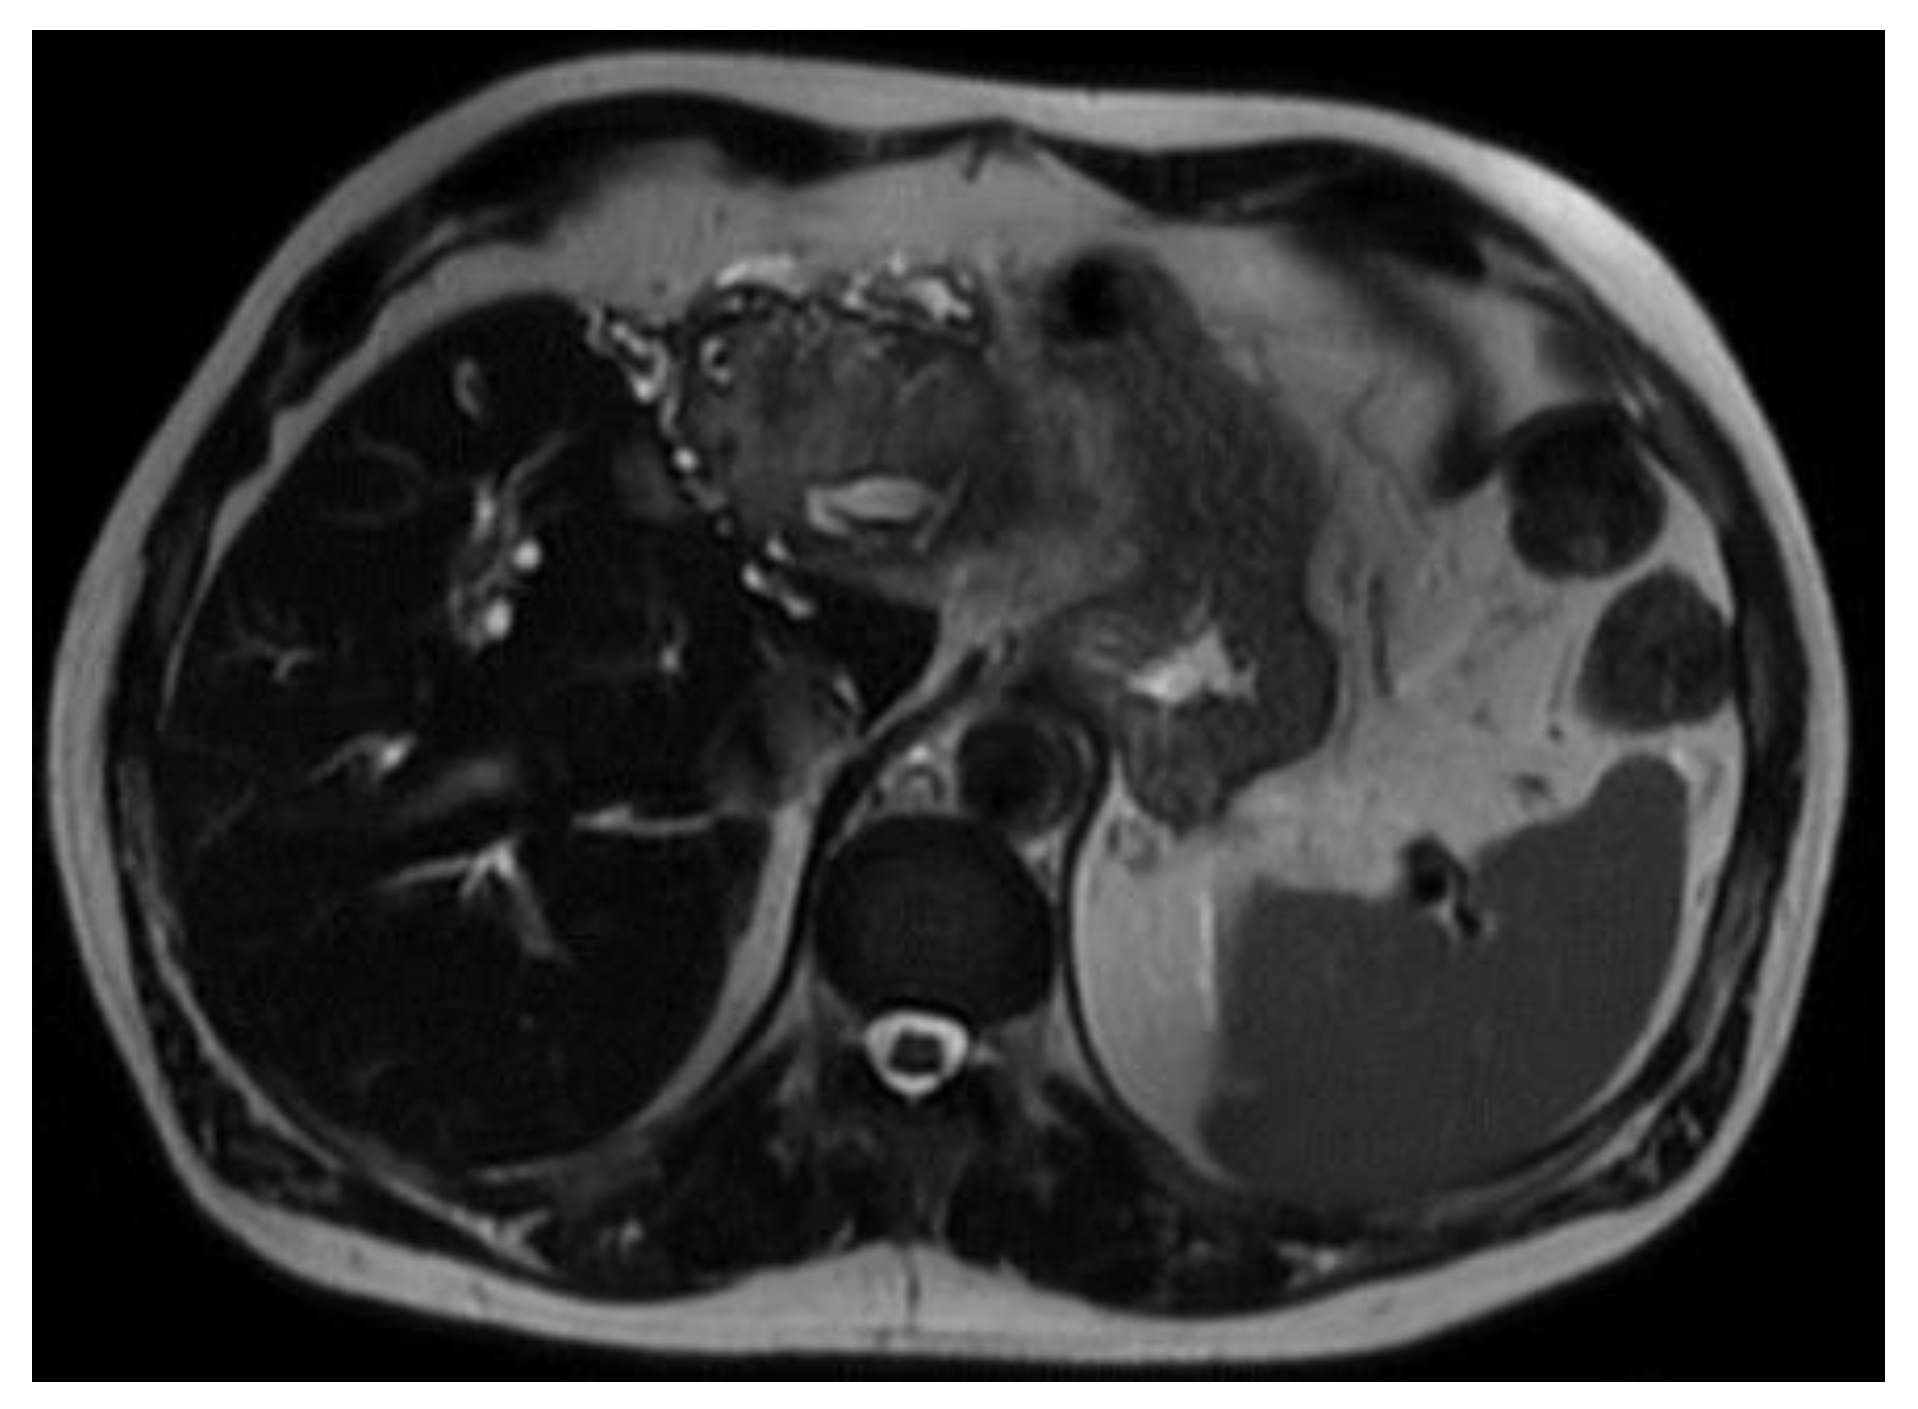

In preparation for the procedure, it was noted that the patient had endorsed lethargy over the past few weeks. Additionally, preprocedural routine labs were notable for a direct bilirubin of 2.93 mg/dL. Due to the polypoid and irregular nature of the lesion, his concomitant lethargy, and direct bilirubinemia, a CT scan of the patient’s abdomen and pelvis was performed, which revealed a distal intrahepatic cholangiocarcinoma with involvement of left hepatic lobe (Figure 1) and umbilical induration corresponding to the skin lesion (Figure 2). A magnetic resonance cholangiopancreatography (MRCP) was performed for further characterization of the cholangiocarcinoma, which revealed an intrahepatic cholangiocarcinoma (Figure 3).

Figure 3. MRCP showed an intrahepatic cholangiocarcinoma . .